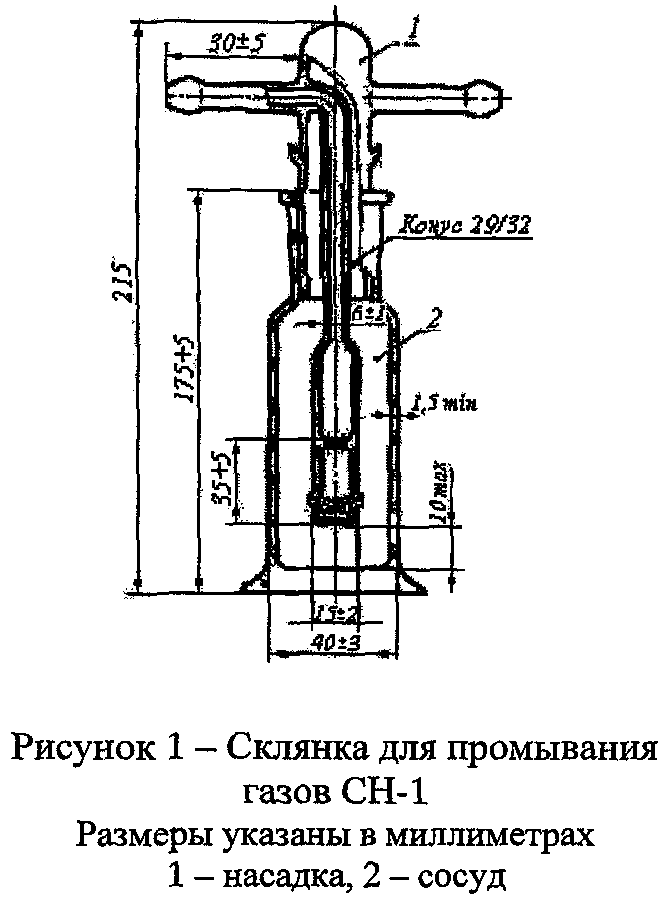

Определение проводят в склянке для промывания газов (рис. 1 или рис. 2).

Перед началом испытания склянку продувают в течение 1-2 мин испытуемым кислородом, который отбирают из баллона через редуктор.

В две одинаковые склянки для промывания газов наливают по 100 мл 5% раствора бария гидроксида (поглотительный раствор).

Испытуемый раствор. Через раствор в одной из склянок пропускают 1000  кислорода в течение 15-20 мин.

Объём кислорода, пропущенный через поглотительный раствор, измеряют с помощью склянки с тубусом (рис. 3) или прибора для отбора проб газа (рис. 4), присоединенного к короткой трубке склянки (рис. 1 или 2) на выходе газа.